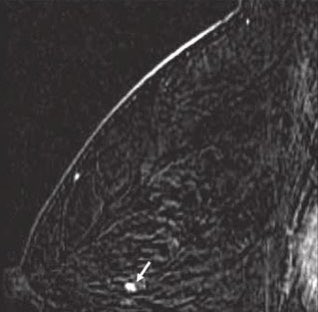

٢-التصوير الشعاعي للثديين

والذي يؤكد على وجود الورم ونوعه الحميد أو المشتبه به ويكون إما بالاشعه الصوتيه للنساء دون ٣٠عاما أو بالماموغرام والصوتيه لل ٣٠عاما وأكبر

8️⃣يميز الفحص الشعاعي بين التكتلات الصلبه والسائلة والتي تدعى بالاكياس وايضا صفاتها التي تشير الى كتلة حميده غير مقلقة أو الى كتلة فيها اشتباه تستدعي إجراء الخزعة

٣- تتم الخزعة بأخذ عينة من نسيج الكتله الصلبه أو شفط لمحتوى الكيسة بأبره وارسالها للمختبر للتأكد من التشخيص